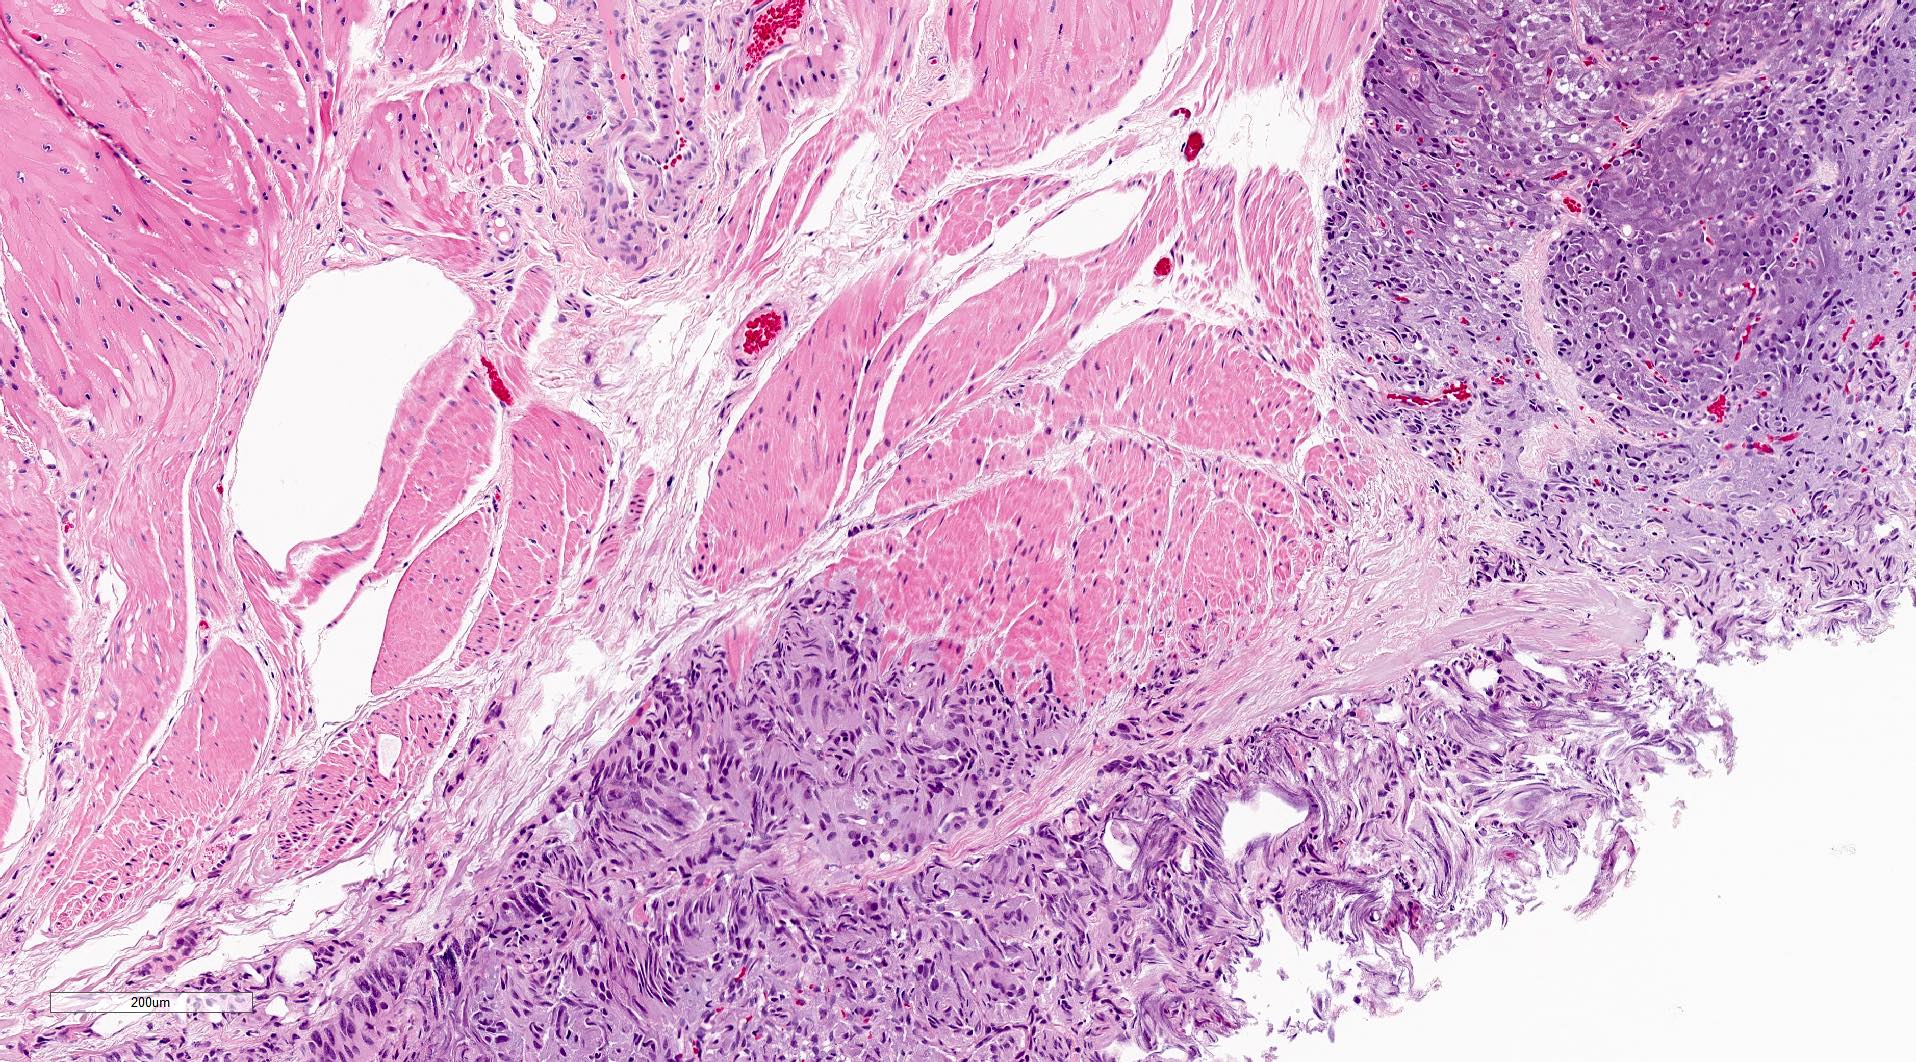

Microscopic (histologic) description

- Typical morphology: epithelioid cells with abundant, eosinophilic / amphophilic, granular cytoplasm and round / ovoid, vesicular / salt and pepper nuclei, arranged in a nested / zellballen pattern and separated by fibrovascular septae with sustentacular cells (Am J Surg Pathol 2004;28:94, World J Clin Cases 2014;2:591, Endocr Pathol 2022;33:90)

Microscopic (histologic) images

Contributed by Theodorus H. van der Kwast, M.D., Ph.D., Michelle R. Downes, M.D., Debra L. Zynger, M.D. and David Cohen, M.B.B.Ch., M.D.

- Microscopic description: This specimen shows an unencapsulated, monomorphous population of round tumor cells in a nested / zellballen pattern with delicate vascular septa and intervening extravasated red blood cells. It predominantly involves the lamina propria of the bladder but in 1 tissue piece clearly involves muscularis propria. The tumor cells have abundant amphophilic cytoplasm and vesicular chromatin with occasional small nucleoli. There is no necrosis, diffuse growth pattern or vascular space invasion identified. The mitotic count is (maximally) 1/10 high power fields. Immunohistochemistry shows the tumor cells to be positive for GATA3 with strong and diffuse expression of synaptophysin and chromogranin, as well as retention of SDHB staining. The tumor cells are negative for AE1 / AE3, HMWK and p63. The Ki67 proliferation index is < 1%. S100 shows faint nuclear and cytoplasmic staining with occasional sustentacular cells identified.

- Microscopic description: Sections show unremarkable surface urothelium with a lesion in the deep lamina propria comprised of large eosinophilic cells with hyperchromatic, focally enlarged nuclei with occasional intranuclear inclusions. A fine vascular plexus is identified in some areas. Necrosis and hemorrhage are not identified. Mitotic rate = 1/10 high power fields (field of view [FOV] = 0.55 mm). The lesion extends to the cauterized base of the specimen. Immunostains confirm the lesion expresses synaptophysin, chromogranin and GATA3. SDHB is retained. AE1 / AE3, CD45, p63 and NKX3.1 are negative.